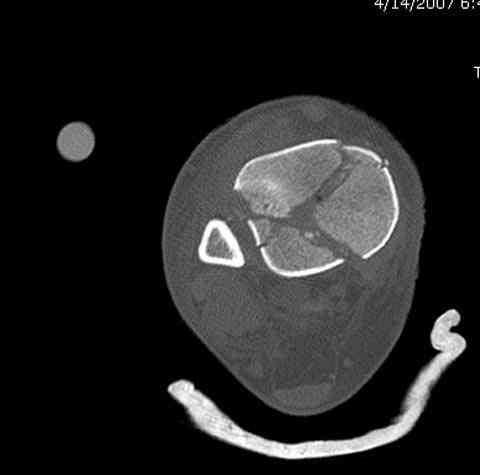

Добавлены КТ снимки. Прошу прощения за качество.

С уважением, Коваленко А.Н.